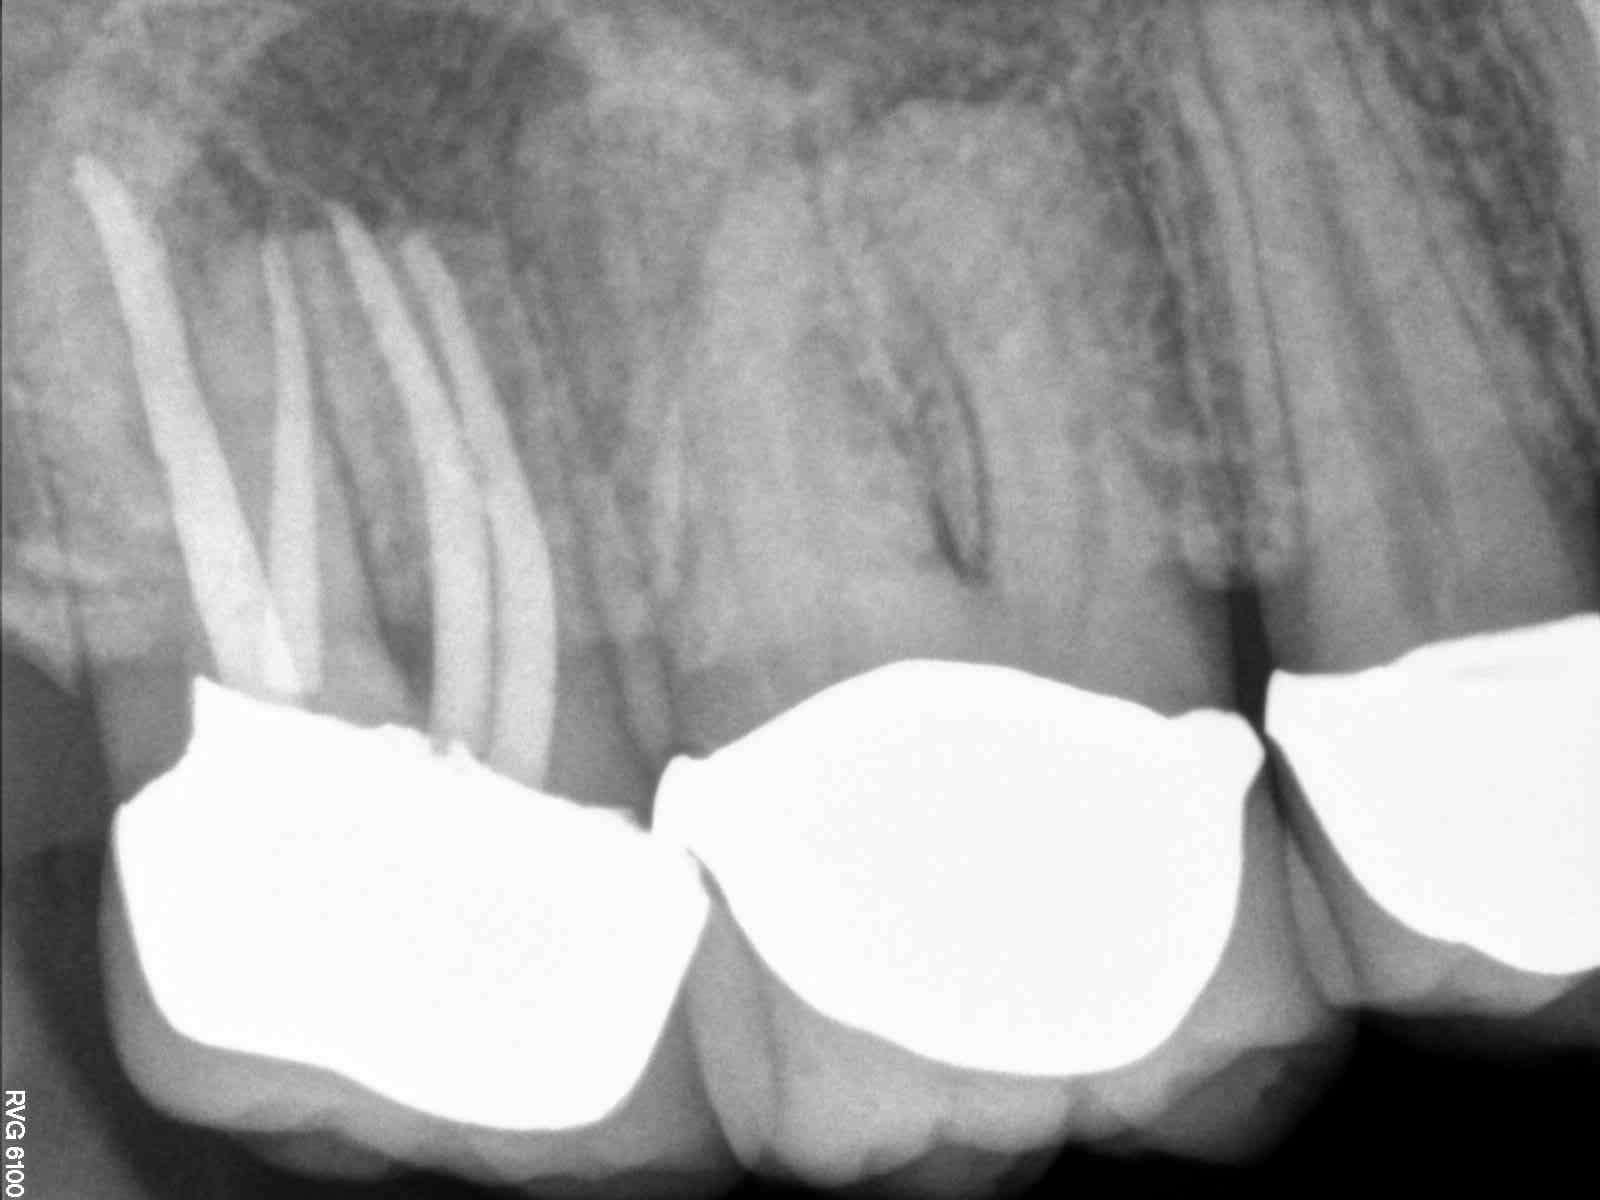

Eventually I will track this also. This case was done in 5/09. In future I will link to original post also. This tooth had no clinical signs of fracture. Probings WNL. Draining buccal fistula and pain. PA shows large lesion on buccal root(s). Notes say overfill on MB2 1mm actual about .5mm. I one stepped this, which I never do on a necrotic tooth, not sure why I did here. Also this is before I used EDTA or CHX.

Obviously this had a separate MB2. We choose to extract this tooth

| MB2 was a little overfilled |